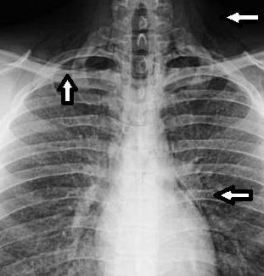

Chest x-ray films revealed diffuse parenchymal haziness and air tracking into the soft tissues of the neck, axilla, and the mediastinum (Figure 1). CT scan of the thorax revealed diffuse homogeneous distribution throughout both lungs of ground-glass opacities that suggested subacute hypersensitivity pneumonitis. Extensive pneumomediastinum (Figure 2a), and cervical emphysema (Figure 2b) were also noted on CT scan.

Figure 1